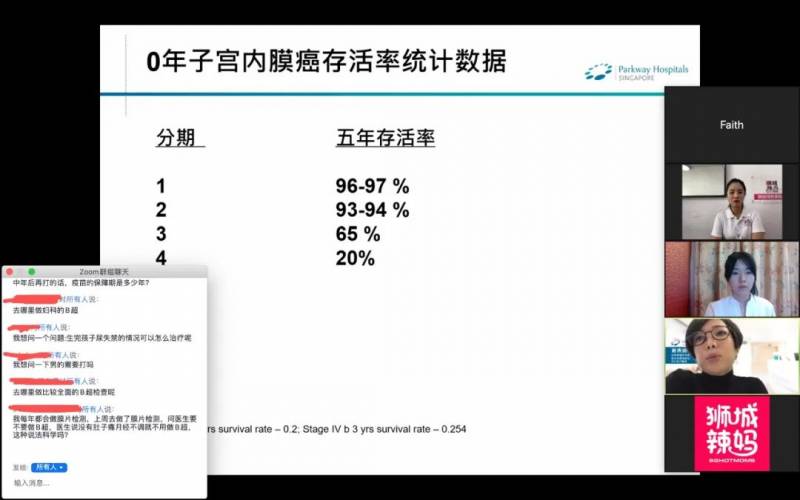

谢医生的主题围绕宫颈癌、子宫癌、卵巢癌等3种女性易得的癌症展开。

子宫内膜癌

子宫内膜癌,全世界每年有接近20万的新发病例,并是导致死亡的第三位常见妇科恶性肿瘤(仅次于卵巢癌和宫颈癌)。

谢医生说,虽然这种癌症最常见于已过更年期的五、六十岁女性。但她诊断过最年轻的子宫内膜癌患者,只有20多岁。因为身体过度肥胖,导致的荷尔蒙大幅度失调引起。

幸运的是,90%子宫内膜癌有阴道异常出血症状,早期可以发现,通过手术方法治疗。